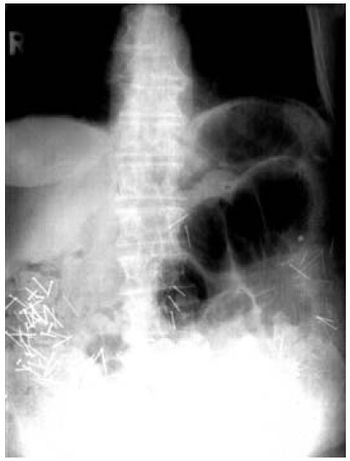

Patient swallows multiple foreign bodies.